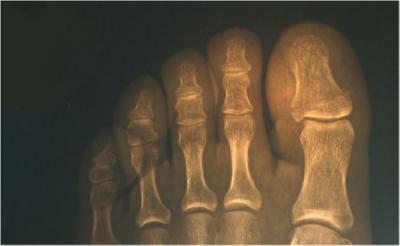

Examination by emergency medical people at a local hospital revealed the diver has a broken toe (comminuted fracture of the left first digital phalange). Basically, the toe was crushed into multiple fragments. Fortunately, this transverse fracture required no pinning or surgery. This type of fracture tends to heal rather well, but this diver missed diving for eight weeks while his body repaired the damage.

The X-rays below of the injury to the diver's left foot show multiple breaks (fine lines) at the in the first bone  (upper right of oblique view) of the big toe

X-Rays of Comminuted Fracture Caused By A Falling Scuba Cylinder

Antero-Posterior View

Enlarged Antero-Posterior View